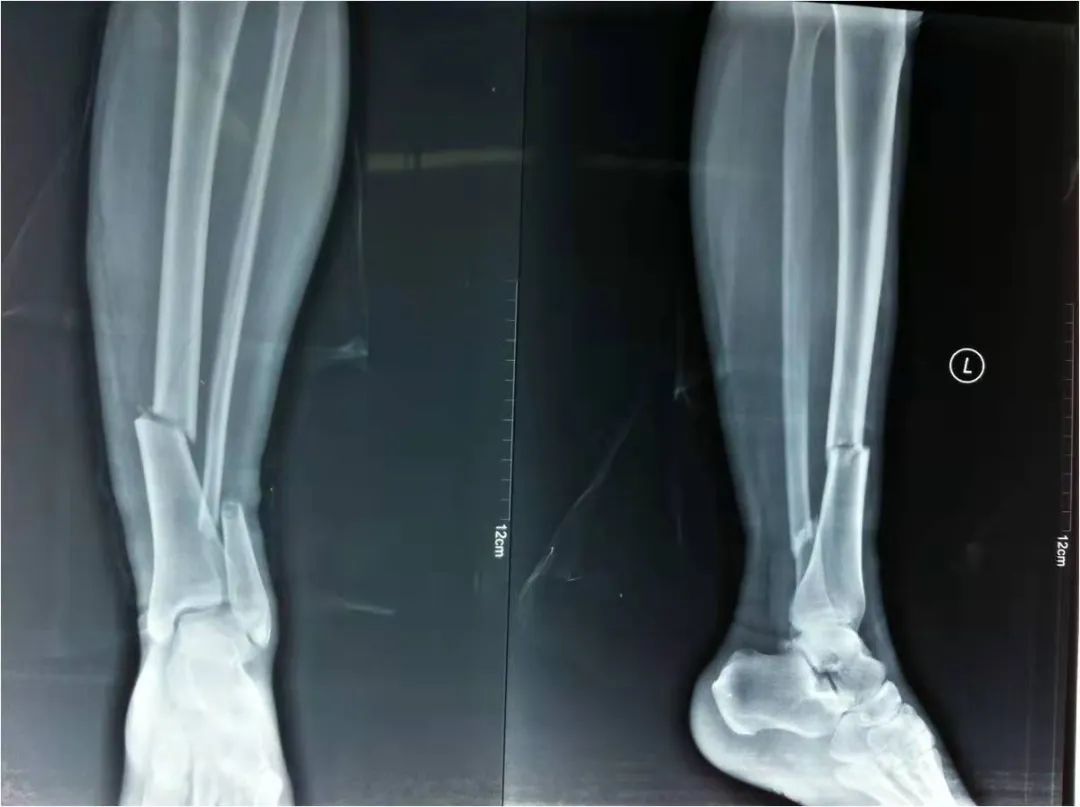

2022年4月22日,我院急救中心接診了一名骨折患者:患者在家不慎摔倒,導致剛做完手術沒多久的脛腓骨再次受創(chuàng),疼痛劇烈傷情加重。骨科呂國福主任迅速給予夾板外固定治療,并給予止疼治療減輕患者疼痛。經診斷患者脛腓骨粉碎性骨折明確,且第一次接骨板釘道仍可見,如不及時手術可能出現骨斷端外露發(fā)展為開放性骨折,可能出現骨筋膜室綜合癥。

如采用傳統(tǒng)手術需大范圍剝離軟組織,手術切口在18公分,損傷面大,影響骨折愈合。經過科內術前討論后與患者及家屬溝通后,呂國福主任決定行小切口微創(chuàng)鈦板植入內固定手術治療,術中植入內固定物并剝離軟組織,此方法對周圍皮膚破壞小,手術切口最小僅0.5公分,極大降低皮膚壞死及后期出現骨不連發(fā)生幾率,從而達到解剖復位。